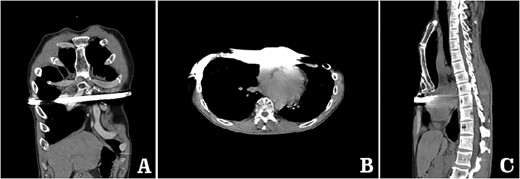

examination showed that the anterior chest wall was sunken and uneven in the middle, and two scars were visible on the lateral chest wall (Fig. 1). The preoperative imaging examination showed that there was a steel bar in the chest wall, and the anterior chest wall was depressed. The lower part of the sternum was broken, with its distal end was supported up by the steel bar. The lower end of the sternum was located deep beneath the steel bar, and the heart was obviously compressed (Figs 2–5). The operation was performed under general anesthesia. Incisions were made in the middle of the depression and two sides of chest wall. After the steel bar was taken out, the adhesion behind the sternum was separated through the median incision. Wung procedure was performed with two steel bars to support the depressed lower part of sternum [4], and then, the third steel bar was used to perform Wenlin procedure to flatten the protrusion part of the rib arch [5, 6] (Figs 6 and 7). During the two procedures, Wang technique was used to fix all the steel bars [7]. After the two procedures were completed, drainage tubes were placed in bilateral thoracic cavities and median surgical field, and the incision was closed to end the operation (Fig. 8). The operation time was 90 min, and the operation was smooth without any complications. The appearance of chest wall returned to normal after the operation, and imaging examination showed that the position of steel bars was satisfactory (Figs 8 and 9). The patient was discharged 7 days after operation.

Computed tomography examination before operation. (A) Coronal view; (B) sectional view; and (C) sagittal view.